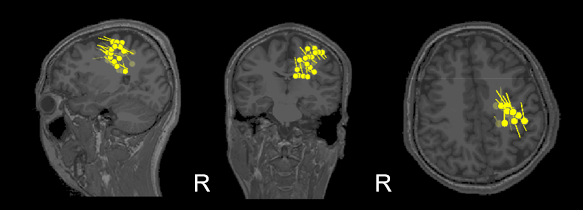

该名癫痫患者此前多次脑影像检查均未能明确病灶位置,术前评估陷入僵局。为完善术前评估,我院脑磁图成像中心为其进行了1小时的静息态MEG数据采集。结果显示,MEG不仅清晰捕捉到棘波样放电(图1),且将病灶溯源定位于左侧脑区(图2),为后续手术提供了关键依据。

2 棘波溯源结果